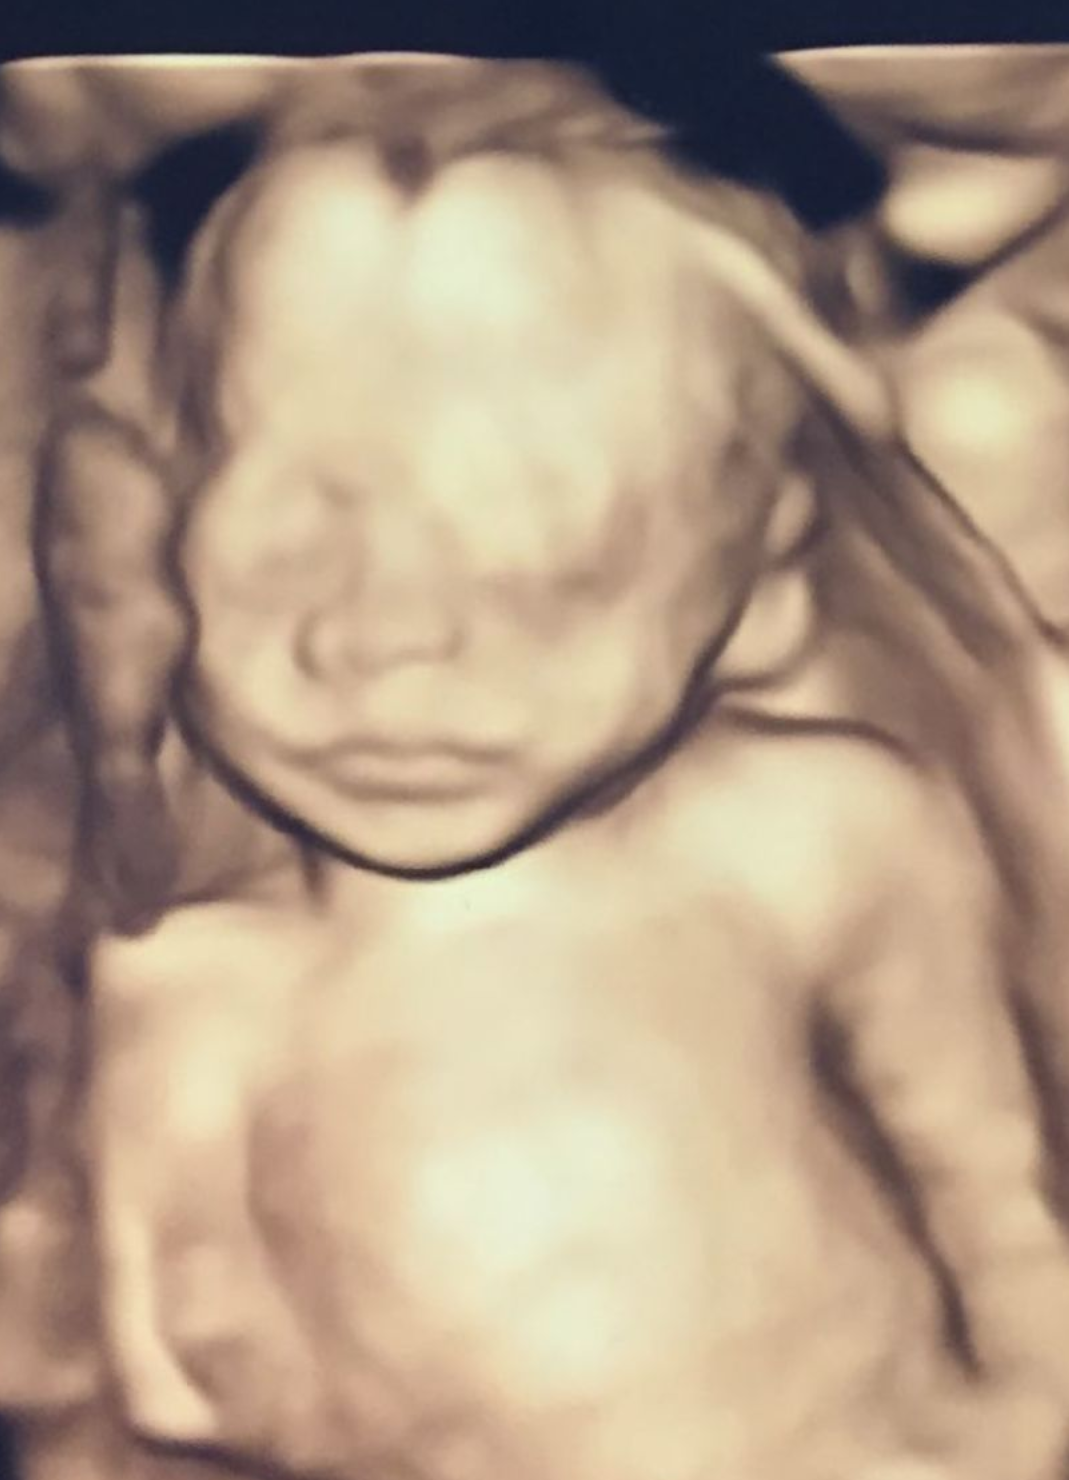

毎回、経膣超音波検査で子供たちを見せてくれました。

すごいですよね。こんな感じで3人とも動いています。

心臓の拍動が見えます!生きてます!

6か月くらいするとこんなかんじ!3Dで輪郭を見たりできるんですね!